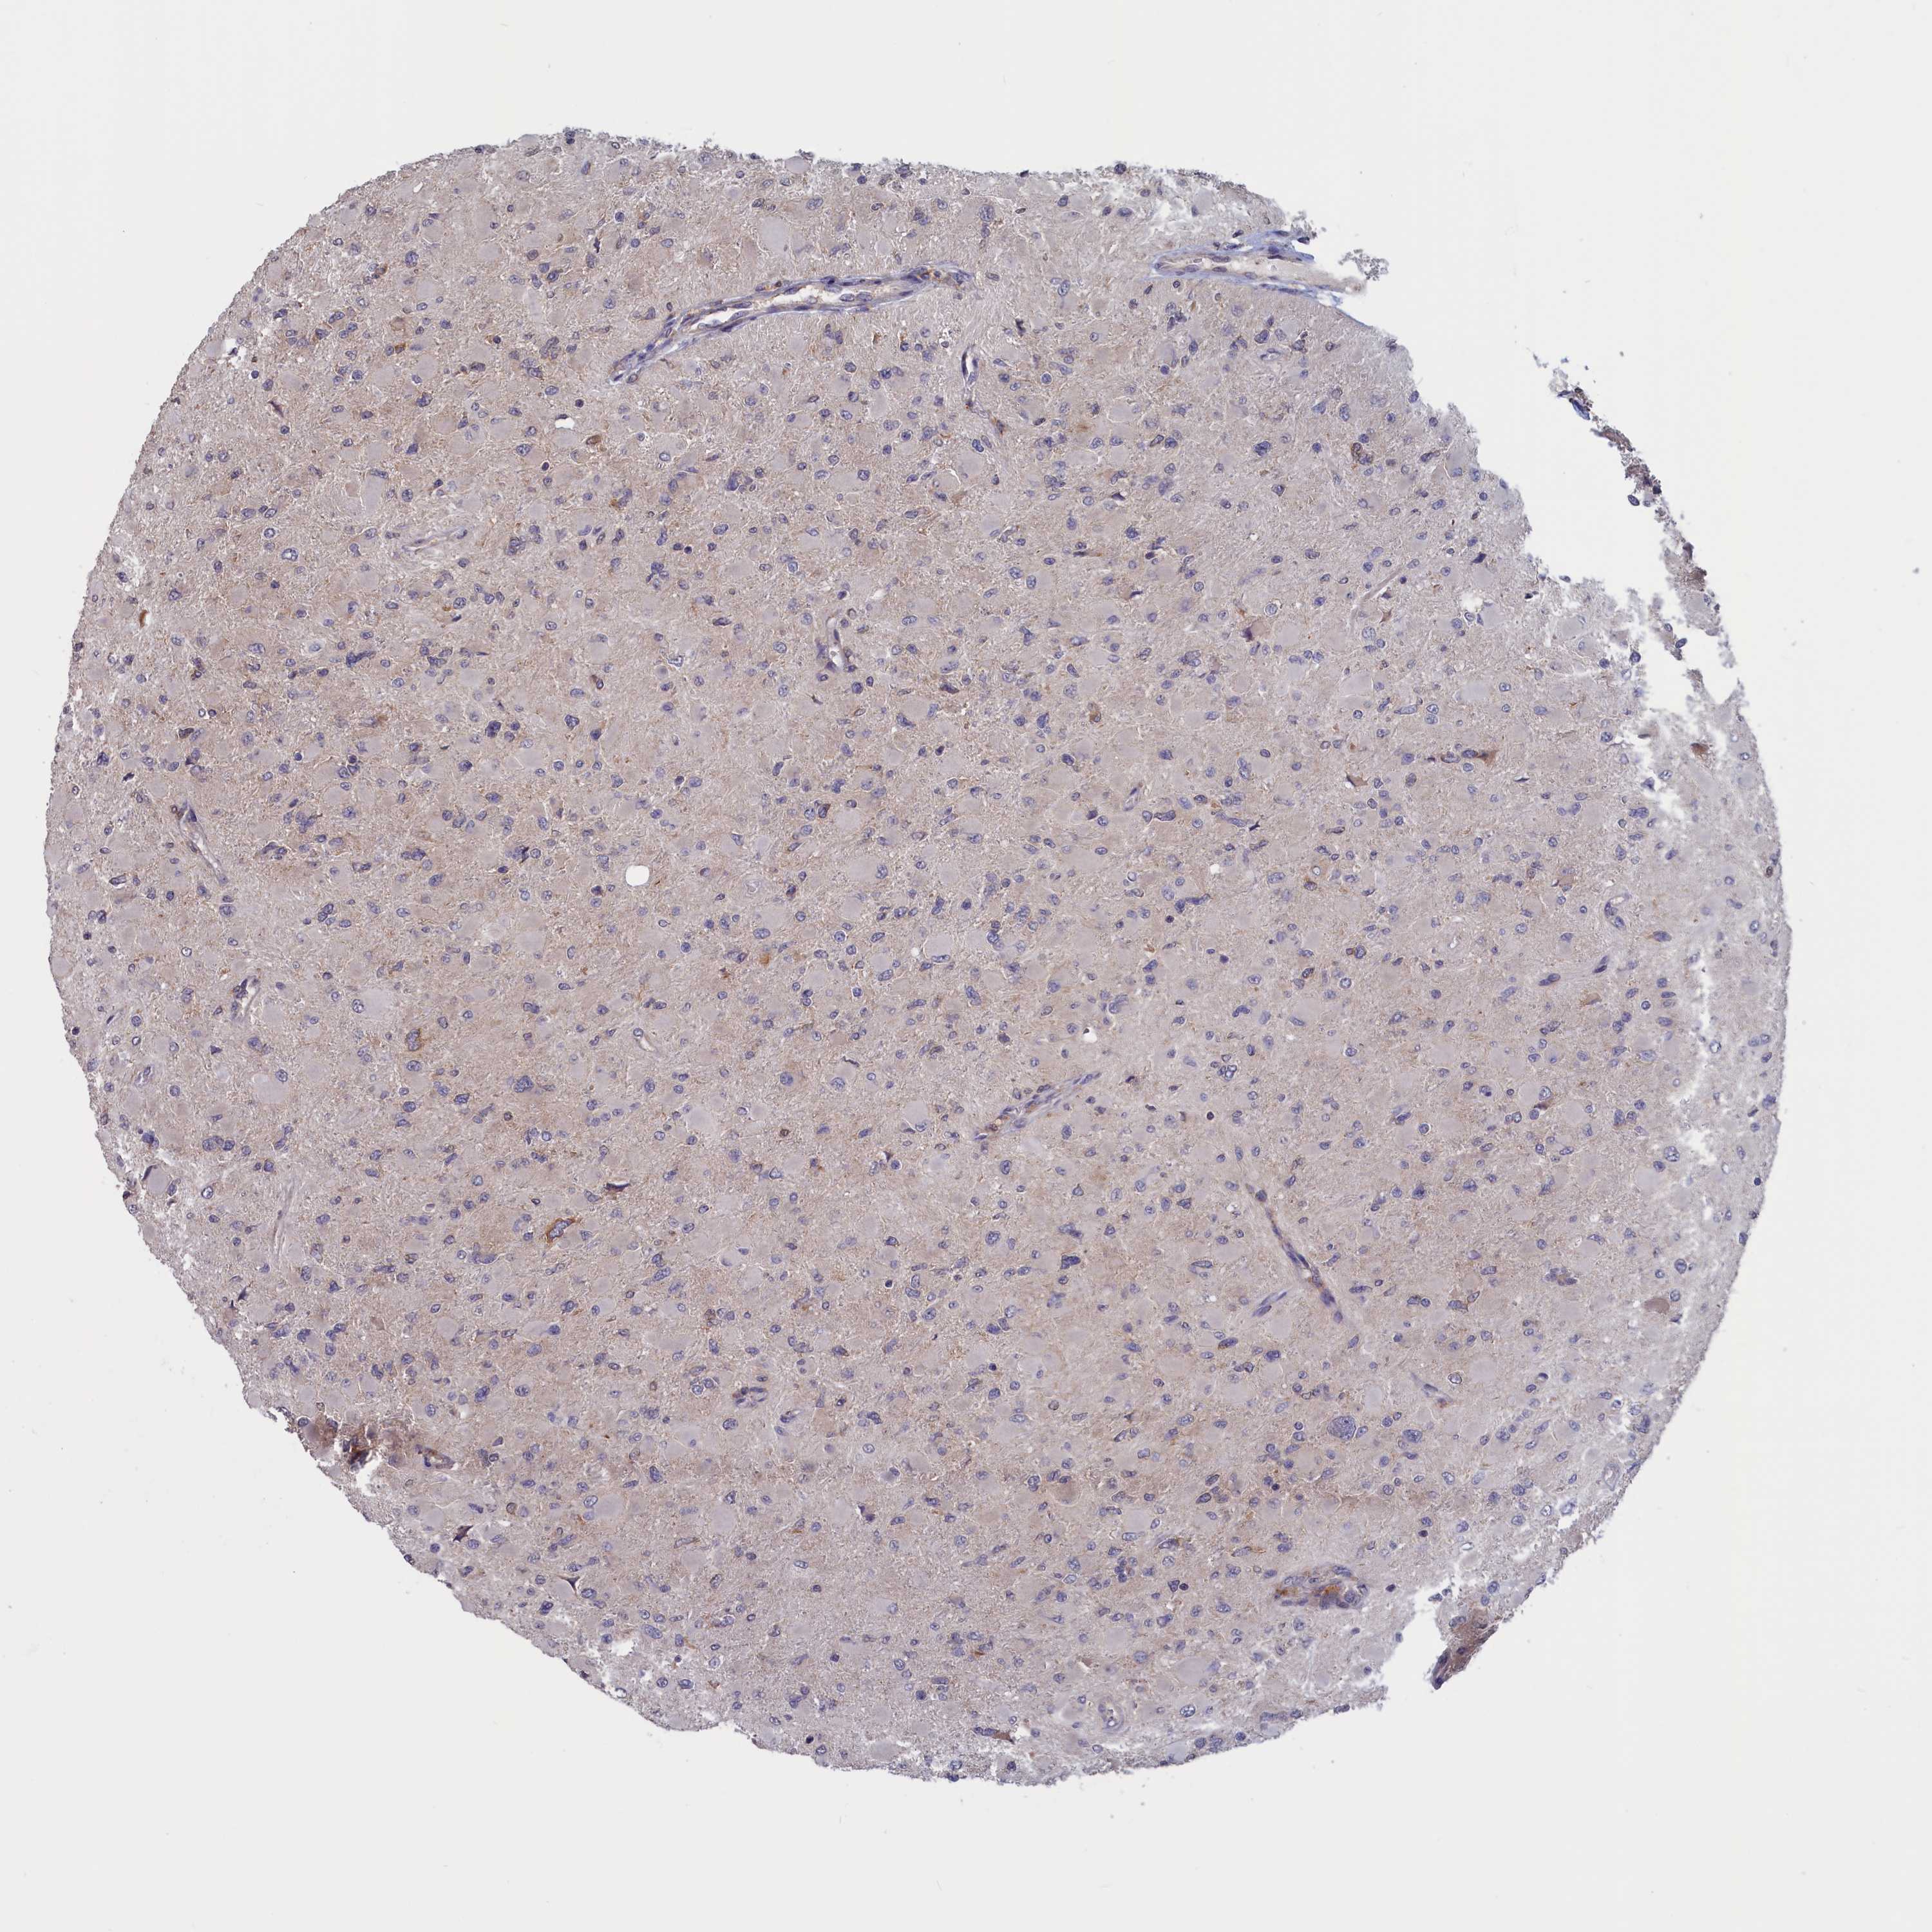

GLIOMA - Protein expressioni

A mouse-over function shows sample information and annotation data. Click on an image to view it in a full screen mode. Samples can be filtered based on level of antibody staining by selecting one or several of the following categories: high, medium, low and not detected. The assay and annotation is described here.

Note that samples used for immunohistochemistry by the Human Protein Atlas do not correspond to samples in the TCGA dataset.

Antibody stainingi

Antibody staining in the annotated cell types in the current human tissue is reported as not detected, low, medium, or high, based on conventional immunohistochemistry profiling in selected tissues. This score is based on the combination of the staining intensity and fraction of stained cells.

Each image is clickable and will lead to virtual microscopy that enables deeper exploration of all samples and also displays staining intensity scores, fraction scores and subcellular localization as well as patient and tissue information for each sample.

Antibody HPA042504

Antibody HPA042548

Staining

High

Medium

Low

Not detected

Intensity

Strong

Moderate

Weak

Negative

Quantity

>75%

75%-25%

<25%

None

Location

Nuclear

Cytoplasmic/membranous

Cytoplasmic/membranous,nuclear

Glioma, malignant, High grade

Glioma, malignant, Low grade